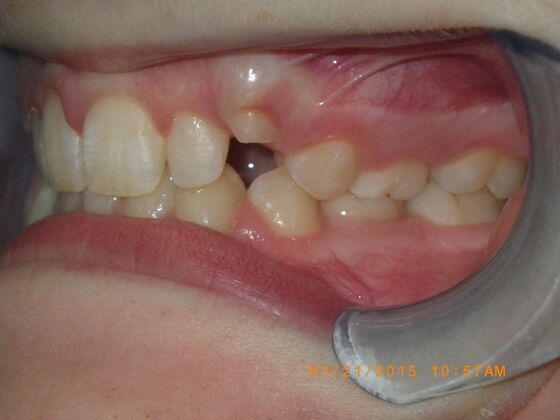

This case presents with a dental midline discrepancy. The upper incisors are tipped toward the palate, which prevents the lower incisors from establishing proper arch form. The upper right molar has drifted forward, causing the upper midline to be skewed to her left. By distalizing the upper left molar, we can correct the midline discrepancy. Lastly, both upper and lower arches need expansion. All of this was completed with conventional straight wire appliances within 2 years.